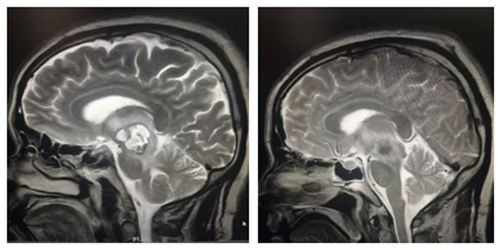

术前肿块影像                                                术后全切影像

今年40多岁的患者葛某是一位大货车司机,今年三月中旬在云南省驾驶货车途中突发剧烈头痛,致使左侧肢体瘫痪,言语不清。所幸及时送医,随后诊断为脑干区海绵状血管瘤并出血,手术风险难度极大,如再次出血则凶多吉少。几经周折,患者找到中南大学湘雅三医院神经外科王知非教授团队,王知非教授团队为其制定了详细周密的手术方案。3月30日,在全麻插管下为患者成功实施了右侧脑干丘脑血管畸形切除及血肿清除术。术后患者恢复良好,偏瘫言语不清等症状得到了明显改善,目前已出院前往康复医院继续后期康复。